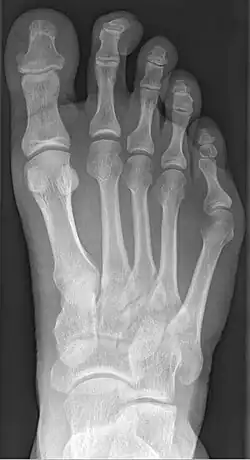

Radiograph showing a tailor's bunion

Tailor's bunion is easily diagnosed because the protrusion is visually apparent. X-rays may be ordered to help the surgeon find out the severity of the deformity.